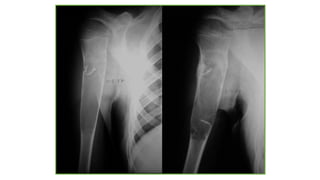

SARCOMA DE EWING

TUMORES MALIGNOS:

Sarcoma de Ewing:

Segundo más frecuente.

10 - 15 años.

Dolor y tumefacción local.

Orden frec.:fémur, tibia, peroné, pelvis.

Metafisarios.

Metástasis al diagnóstico en 30%.: pulmón, hueso, adrenales,

cerebro.

60% Lítica, 15% Esclerótica, 25% Mixta.

Rx: permeativo intramedular, engrosamiento cortical, reacción

perióstica, masa partes blandas.

NIÑO 12A.: Lesión lítica

destructiva con masa de

partes blandasen diafisis

femoral izq.